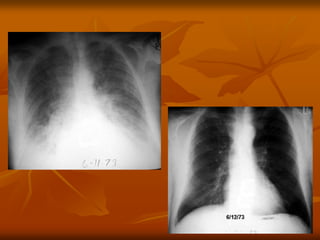

X QUANG PHUØ PHOÅI CAÁP

PHUØ PHOÅI DO NGUYEÂN NHAÂN TIM

(CARDIOGENIC PULMONARY EDEMA)

41

-Redistribution.

-Diffuse bilateral interstitial

edema.

MYOCARDIAL INFARCTION

TRANSVENOUS PACEMAKER

-The lungs are now clear.

-Normal pulmonary

vasculature.